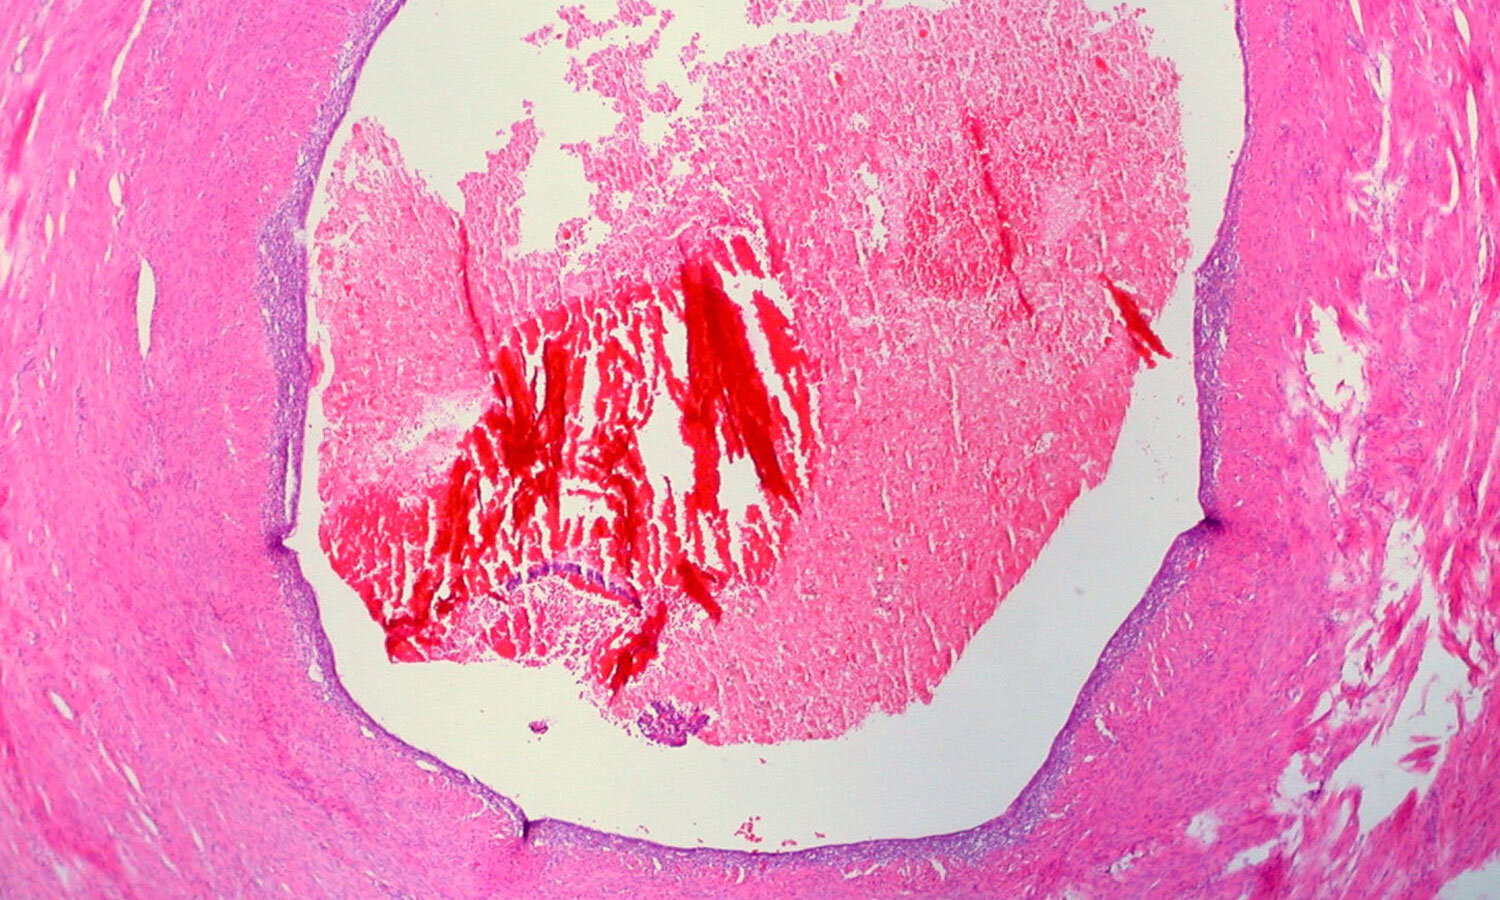

Endometriosis is a painful condition in which the inner lining of the uterus—the endometrium—starts colonizing its neighbors in the pelvic cavity. The endometrium is the thing that thickens, breaks down, and then bleeds out every month. So having endometriosis is like having multiple periods—not just from your womb, but from a bunch of other parts on your insides. (I don’t even have a period, but I’m getting crampy and bloated just thinking about this.)

The most common target is the ovaries, but endometriosis can affect the peritoneum, bladder, intestines—any of that viscera stuff.